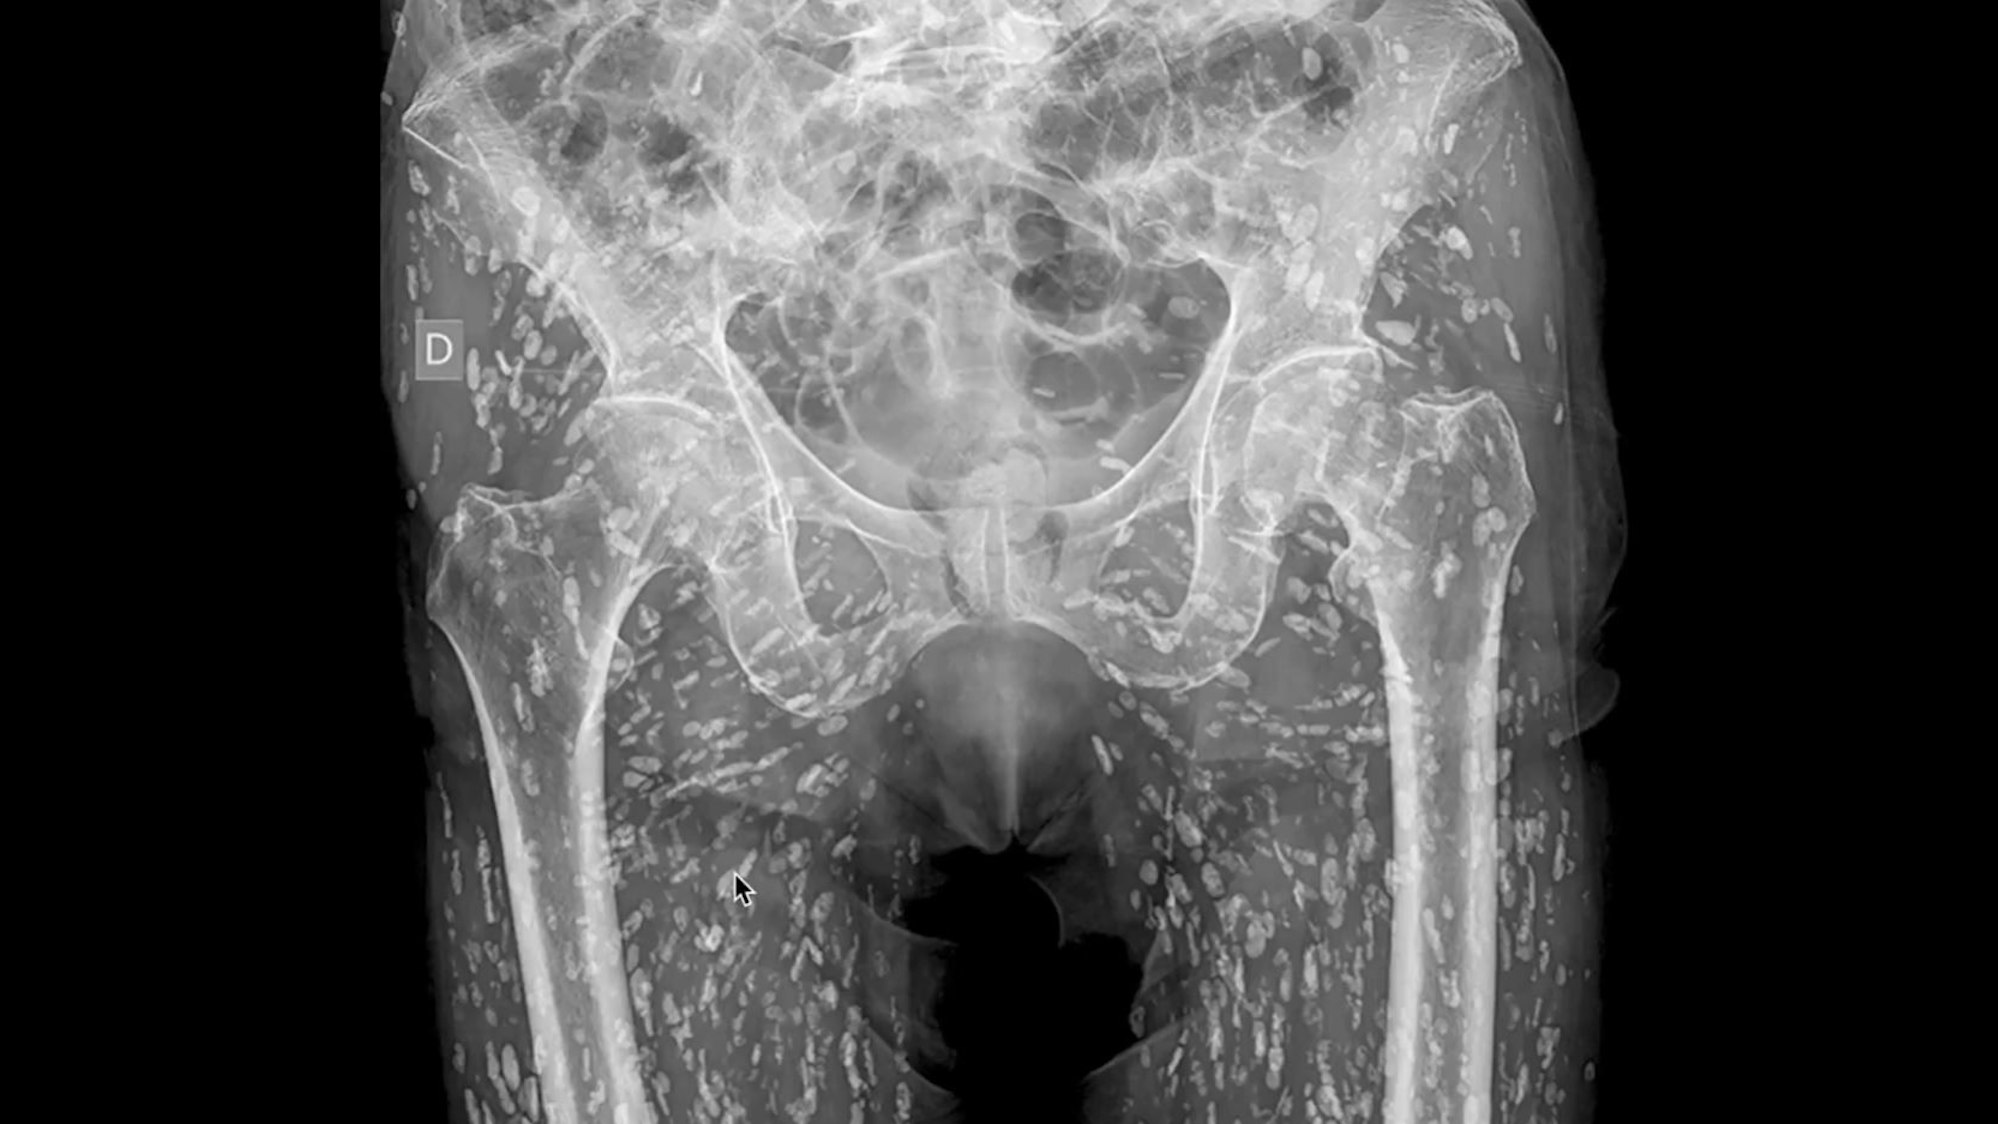

Zu sehen sind auf diesem im Januar 2025 von Sam Ghali auf X veröffentlichten Röntgenbild der Beckenbereich und die Oberschenkel einer Person, die von Parasiten befallen sind.

Zu sehen bekamen die Fachleute auf den Röntgenbildern den Beckenbereich und die Oberschenkel. Doch die eigentliche Sensation: unzählige kleine, weiße Flecken. Diese sind keine technischen Fehler – sondern um Larvenzysten des Schweinebandwurms, auch bekannt als Taenia solium. Diese Zysten können sich zu Tausenden im menschlichen Körper ansammeln.

Wie es zu dem Fund kam? Die betroffene Person suchte aufgrund von Hüftschmerzen eine Klinik auf. Ein Bruch im Hüftgelenk führte zu der Entdeckung von Parasiten auf dem Röntgenbild – ein Zufallsfund.